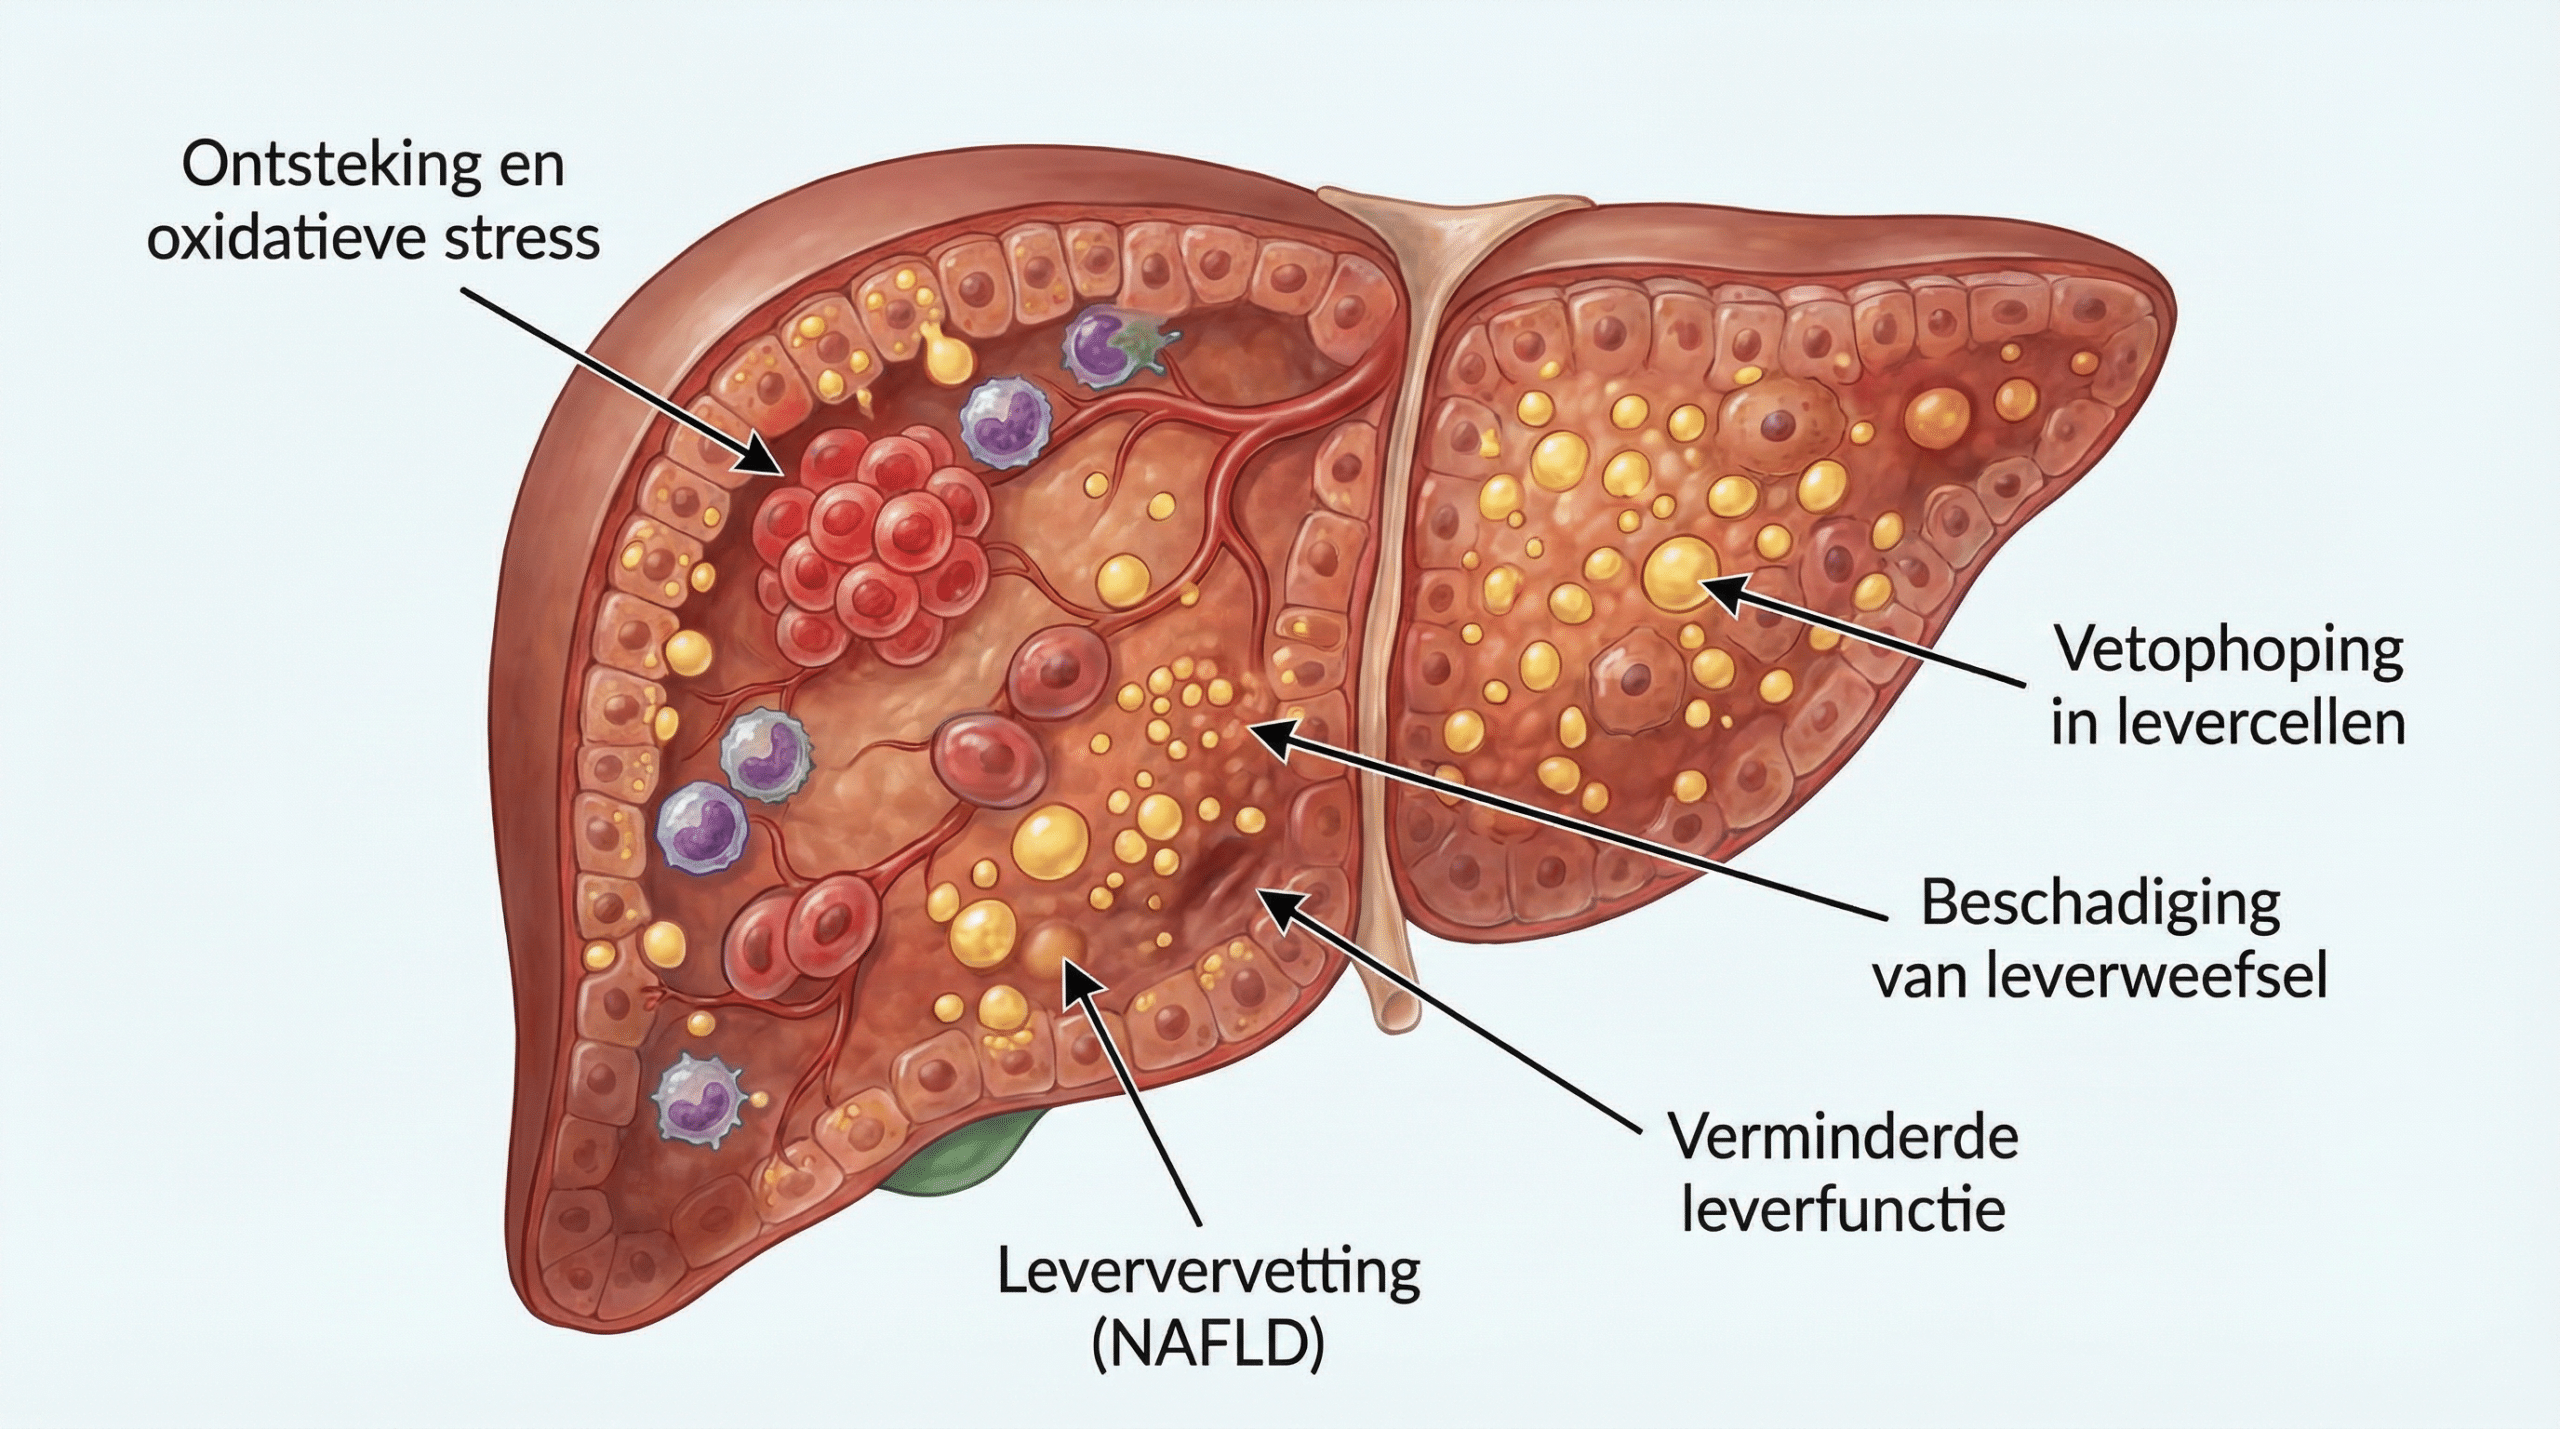

Om het verschil te begrijpen, moeten we eerst begrijpen hoe de lever vet verwerkt en wat er misgaat bij leververvetting.

De lever verwerkt normaal gesproken vetten efficiënt — maar wanneer er meer vet binnenkomt dan de lever kan verwerken, begint het overtollige vet zich op te stapelen in de levercellen zelf.

Kijk nu naar een aangetaste lever.

Door vetopstapeling raken levercellen beschadigd — de kleine vetdruppeltjes in de cellen verstoren de normale leverfunctie, veroorzaken oxidatieve stress en activeren ontstekingsreacties die de schade verder uitbreiden.

Het is als een overbelaste fabriek die haar eigen afval begint op te slaan.

Op een gegeven moment raakt het systeem verstopt — en begint de schade zich uit te breiden naar het omliggende leverweefsel.